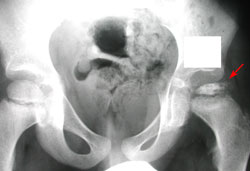

In this x-ray, Perthes disease has progressed to a collapse of the femoral head (arrow). The other side is normal.

Courtesy of Texas Scottish Rite Hospital for Children